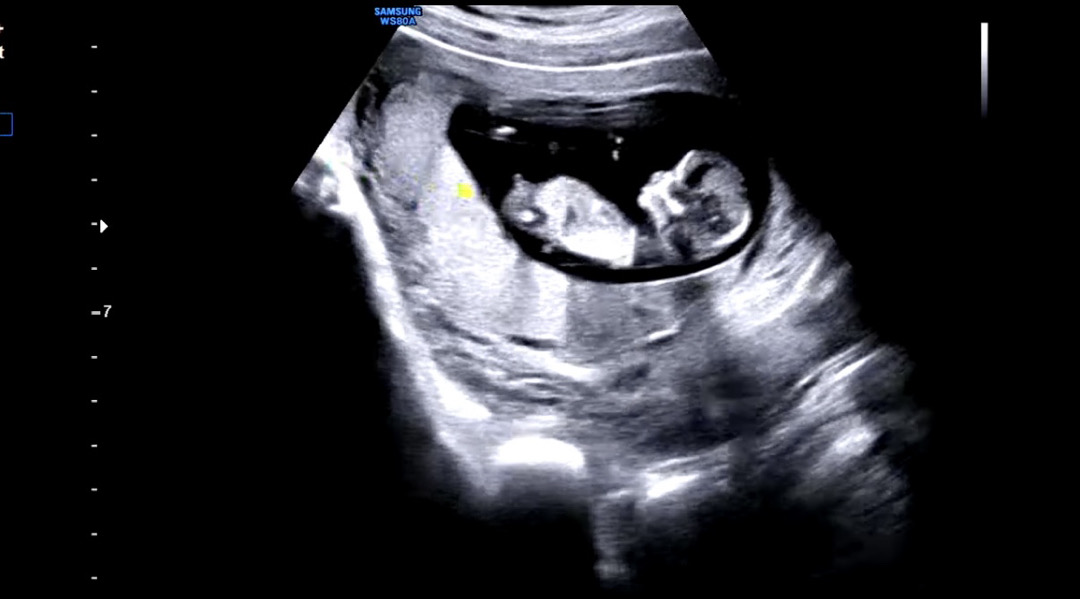

12주 초음파 아들일까요?

12주 초음파인데 저 튀어나온 부분이 아들일까요?ㅎㅎ